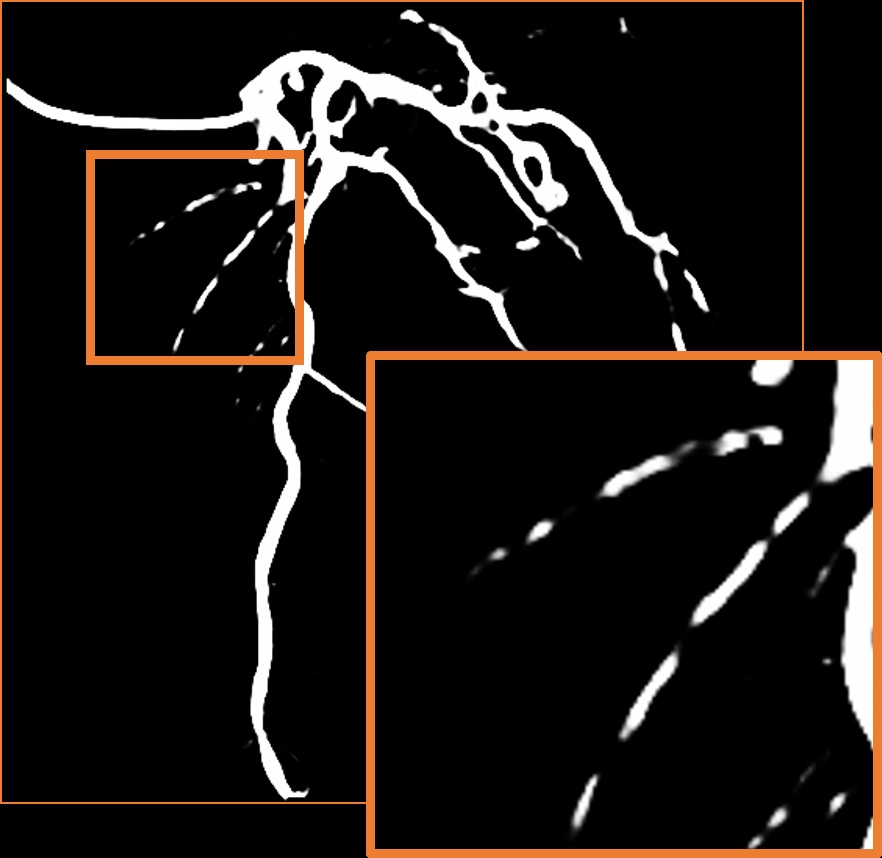

A.2 Temporal Coherency

Our method takes an entire X-ray video as input, thus producing segmentation results with better temporal coherency. Temporal coherency is essential for making medical diagnoses, especially when dealing with blood flow in vessels. Therefore, we conduct visual comparisons between our method and other compared methods by slicing horizontally or vertically and stacking the segmentation results. The results in Figure 11 show our method strikes a better balance between segmentation accuracy and temporal coherency. While other baseline methods either produce false segmentation results or do not maintain consistent prediction along the temporal dimension.